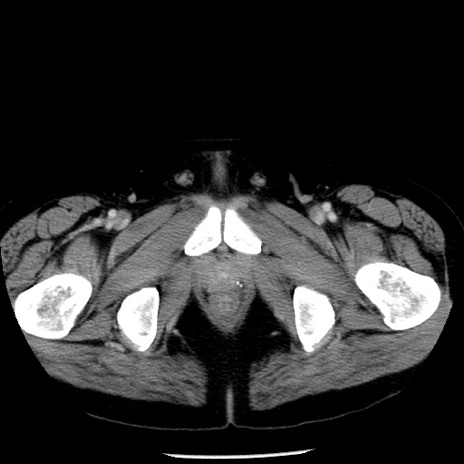

症例29(横断像)

【症例】40歳代男性

【現病歴】2日前から胃痛あり。徐々に周期的な激痛に変化した。本日になっても激痛があるため受診。

【身体所見】意識清明、BT 38-39℃台あり、腹部:膨満、やや硬、右下腹部に圧痛あり。

【データ】WBC 8500、CRP 23.26